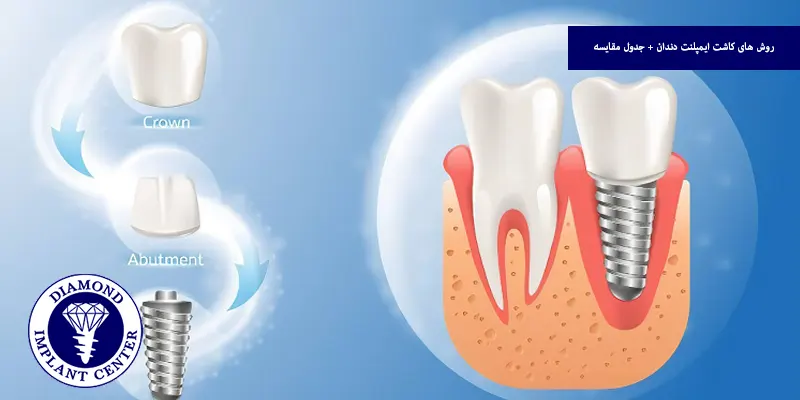

کاشت ایمپلنت دندان یکی از پیشرفته ترین و ماندگارترین روشها برای جایگزینی دندان های از دسترفته است، اما آیا همه روش های کاشت ایمپلنت یکساناند؟ پاسخ منفی است، بسته به وضعیت استخوان فک، سلامت عمومی بیمار و نیازهای فردی، روش های مختلفی برای کاشت ایمپلنت وجود دارد؛ از روش کلاسیک دو مرحلهای گرفته تا تکنیکهای نوینی مانند ایمپلنت فوری یا دیجیتال که در این مقاله قصد داریم با معرفی و مقایسه انواع روش های کاشت ایمپلنت، به شما کمک کنیم تا بهترین گزینه را انتخاب کنید، کدام روش برای شما مناسبتر است؟

انتخاب روش مناسب کاشت ایمپلنت نقش مهمی در موفقیت نهایی درمان، دوام ایمپلنت و رضایت بیمار دارد، هر بیمار شرایط منحصر به فردی دارد؛ مانند تراکم استخوان، وضعیت لثه، سن، سابقه بیماریها و حتی بودجه مالی و انتخاب نادرست روش منجر به جوش نخوردن ایمپلنت، عفونت یا نیاز به جراحی مجدد میشود، از طرفی روش مناسب روند درمان را کوتاهتر، کمتهاجمیتر و با نتایج طبیعیتر همراه میکند، بنابراین مشاوره با متخصص مجرب و بررسی دقیق وضعیت دهان و فک، کلید انتخاب بهترین روش ایمپلنت برای هر فرد است.